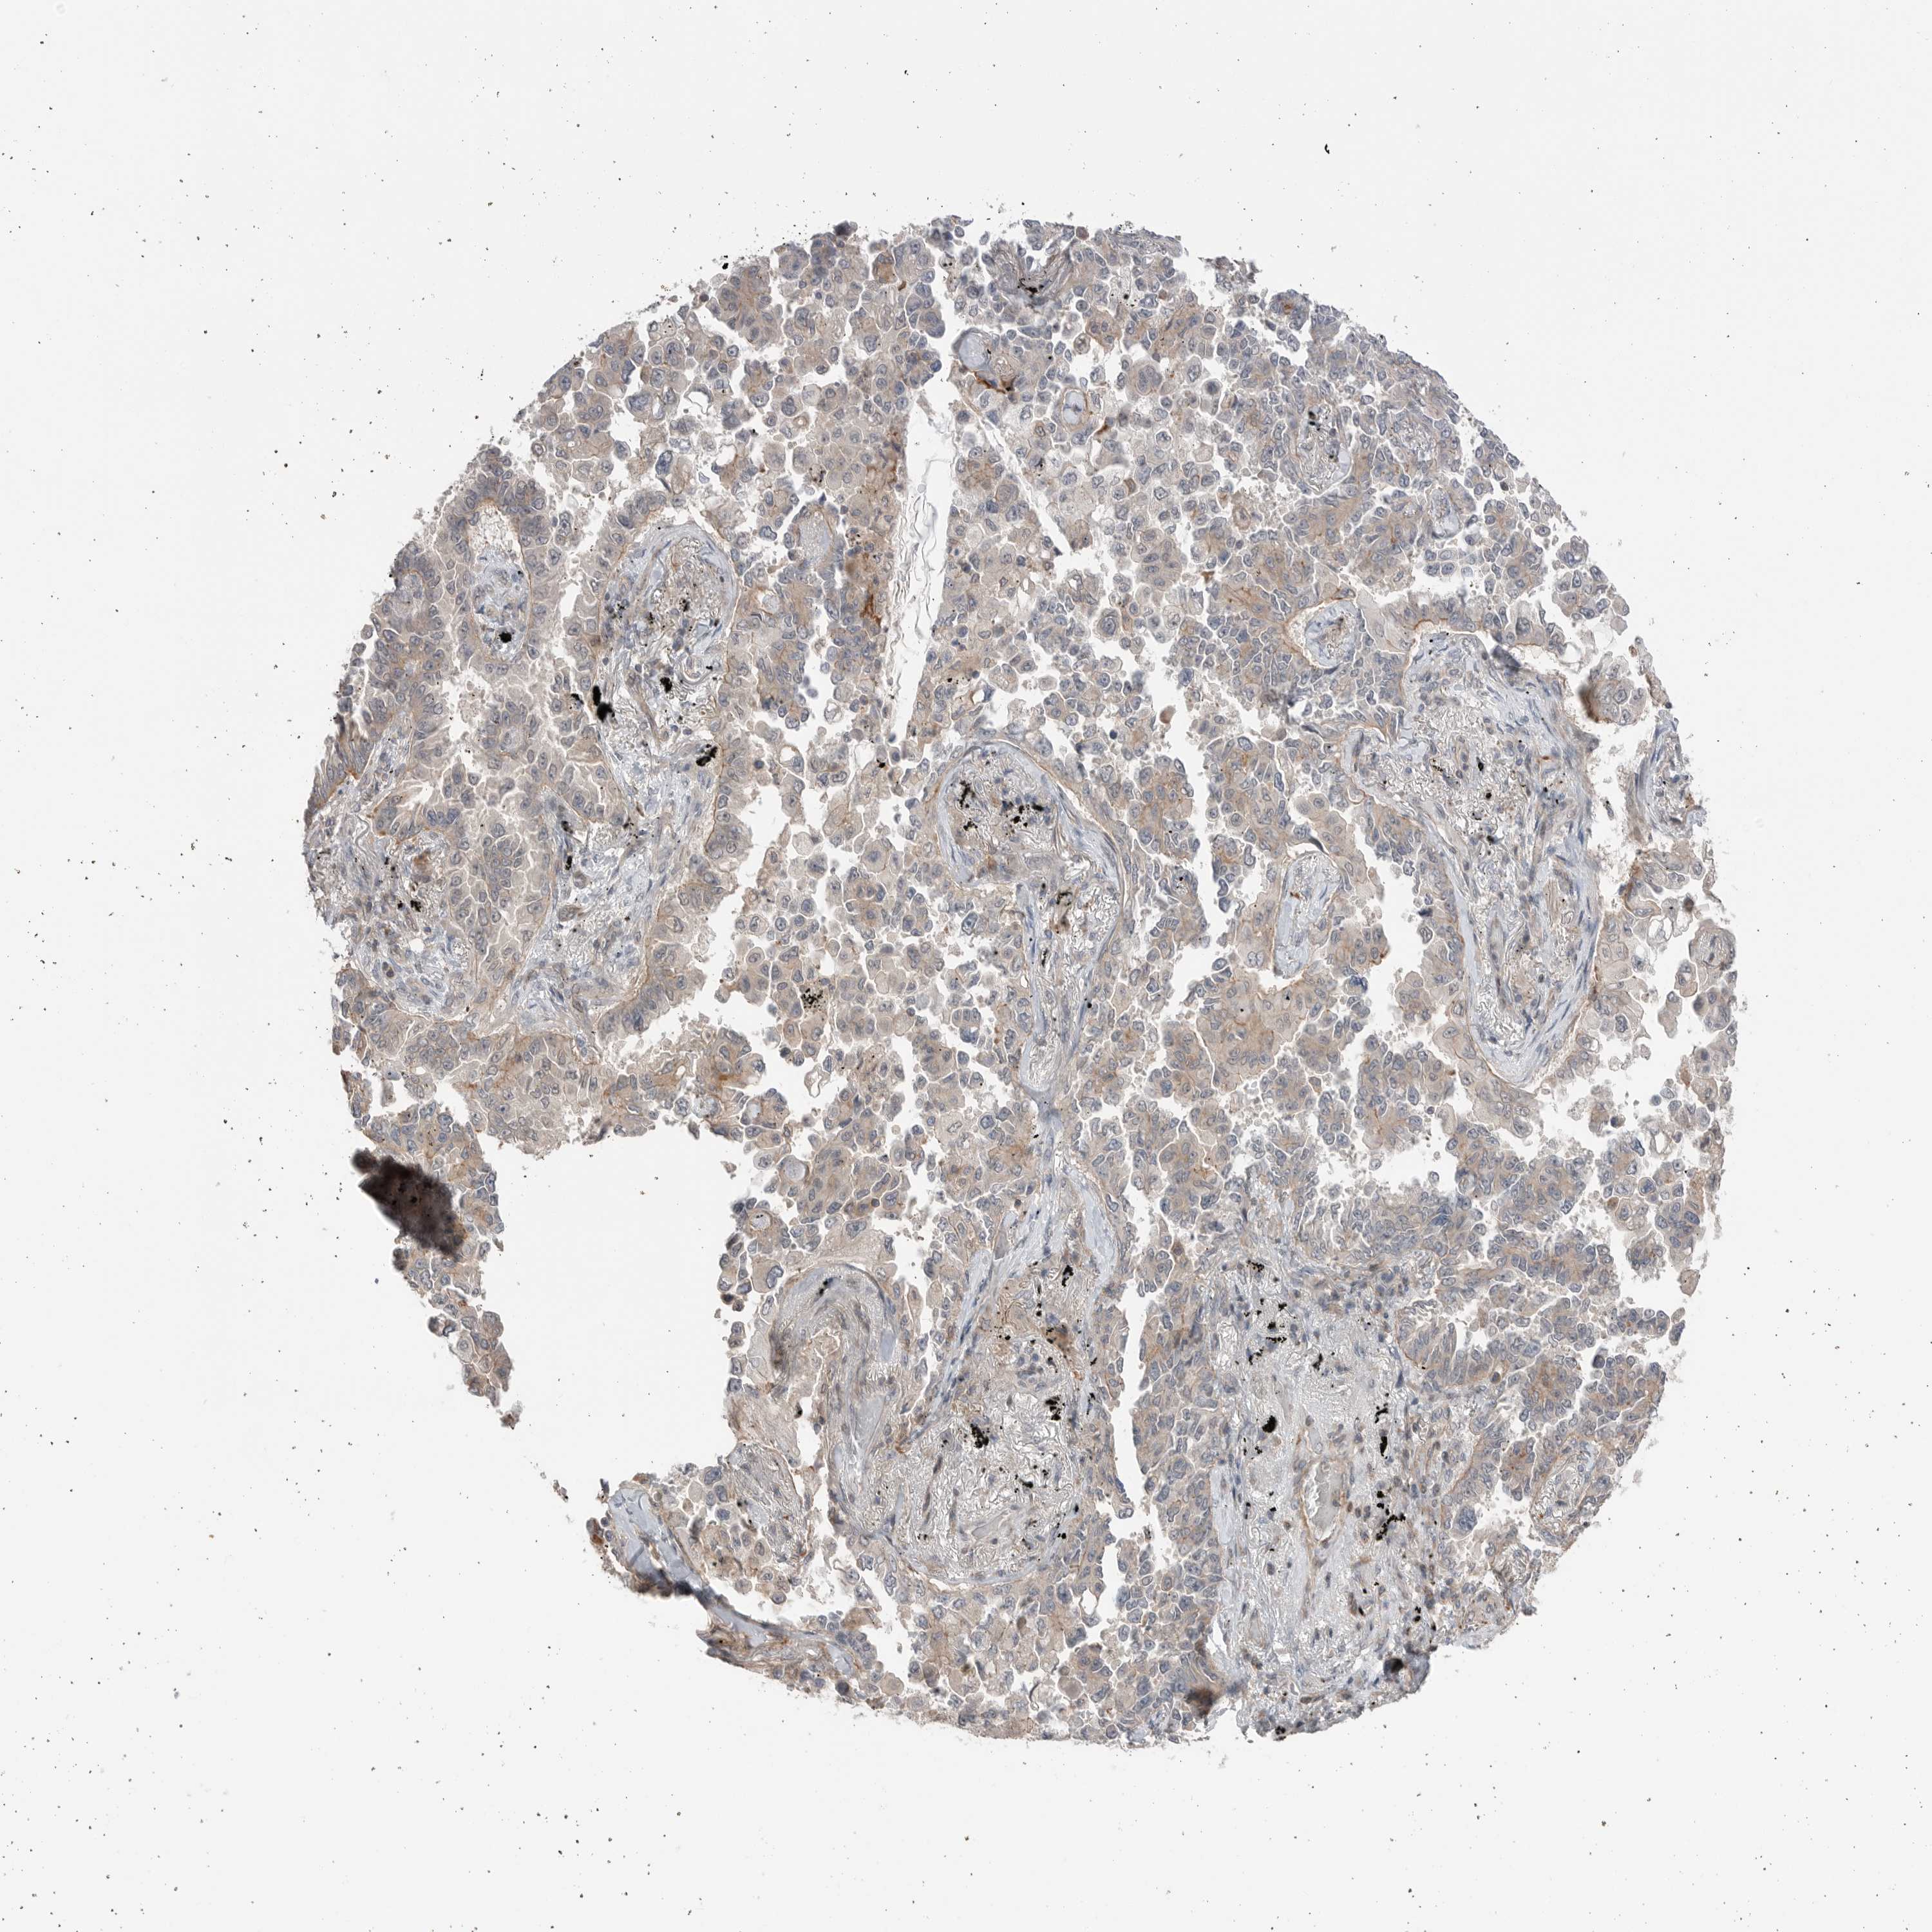

LUNG SQUAMOUS CELL CARCINOMA (TCGA) - Interactive survival scatter ploti

The Survival Scatter plot shows the clinical status (i.e. dead or alive) for all individuals in the patient cohort, based on the same data that underlies the corresponding Kaplan-Meier plots. Patients that are alive at last time for follow-up are shown in blue and patients who have died during the study are shown in red.

The x-axis shows the expression levels (FPKM) of the investigated gene in the tumor tissue at the time of diagnosis. The y-axis shows the follow-up time after diagnosis (years). Both axes are complimented with kernel density curves demonstrating the data density over the axes. The top density plot shows the expression levels (FPKM) distribution among dead (red) and alive patients (blue). The right density plot shows the data density of the survived years of dead patients with high and low expression levels respectively, stratified using the cutoff indicated by the vertical dashed line through the Survival Scatter plot. This cutoff is automatically defined based on the FPKM cutoff that minimizes the p-score. The cutoff can be changed by dragging the vertical line or by entering a cutoff value in the square labeled "Current cut-off".

Under the Survival Scatter plot the p-score landscape (black curve; left axis) is shown together with dead median separation (red curve; right axis). Dead median separation is the difference in median mRNA expression between patients who have died with high and low expression, respectively. It is calculated as follows: median FPKM expression of dead patients with high expression - median FPKM expression of dead patients with low expression. This is intended to aid the user in visually exploring custom cutoffs and the associated p-scores and dead median separation.

Individual patient data is displayed and can be filtered by clicking on one or more of the category buttons on the top of the page. Categories describing expression level and patient information include: high, low, alive, dead, female, male and tumor stages. The scale of the x-axis can be toggled between linear and log-scale by clicking on the "x log" button. Mouse-over function shows TCGA ID, patient information and mRNA expression (FPKM) for each patient.

& Survival analysisi

Kaplan-Meier plots summarize results from analysis of correlation between mRNA expression level and patient survival. Patients were divided based on level of expression into one of the two groups "low" (under cut off) or "high" (over cut off). X-axis shows time for survival (years) and y-axis shows the probability of survival, where 1.0 corresponds to 100 percent.

PEAK1 is not prognostic in Lung Squamous Cell Carcinoma (TCGA)

Best expression cut offi

Based on the FPKM value of each gene, patients were classified into two groups and association between prognosis (survival) and gene expression (FPKM) was examined. The best expression cut-off refers the FPKM value that yields maximal difference with regard to survival between the two groups at the lowest log-rank P-value. Best expression cut-off was selected based on survival analysis .

When clicking on this number, the vertical dashed line indicating cut-off, the interactive survival plot, and the Kaplan-Meier curve will be adjusted to show results based on the best expression cut-off.

: 5.02

P scorei

Log-rank P value for Kaplan-Meier plot showing results from analysis of correlation between mRNA expression level and patient survival.

N/A

TCGA RNA samplesi

RNA-seq data is reported as average FPKM (number Fragments Per Kilobase of exon per Million reads), generated by the The Cancer Genome Atlas (TCGA) .

Normal distribution across the dataset is visualized with box plots, shown as median and 25th and 75th percentiles. Points are displayed as outliers if they are above or below 1.5 times the interquartile range. FPKM values of the individual samples are presented next to the box plot.

Average pTPM 4.3

Number of samples 489